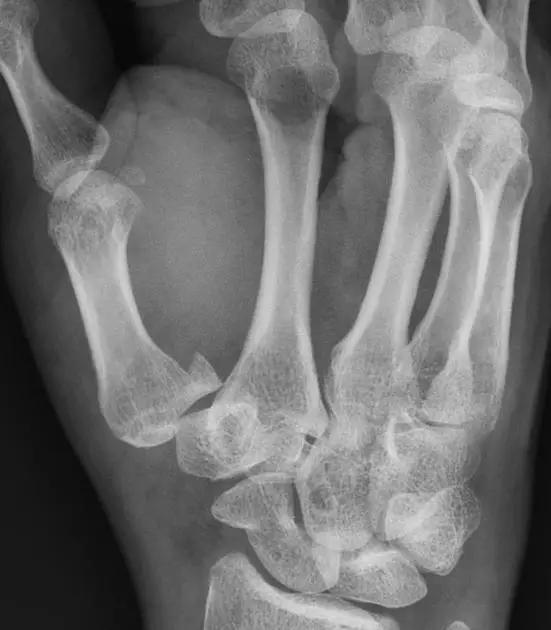

6. Bennett 骨折

第 1 掌骨基底的斜形骨折,掌骨近端形成轴向移位,掌侧边缘形成三角形的骨碎片。

10. Rolando 骨折

第一掌骨基底的 T 或 Y 型粉碎性骨折,可伴有关节半脱位。